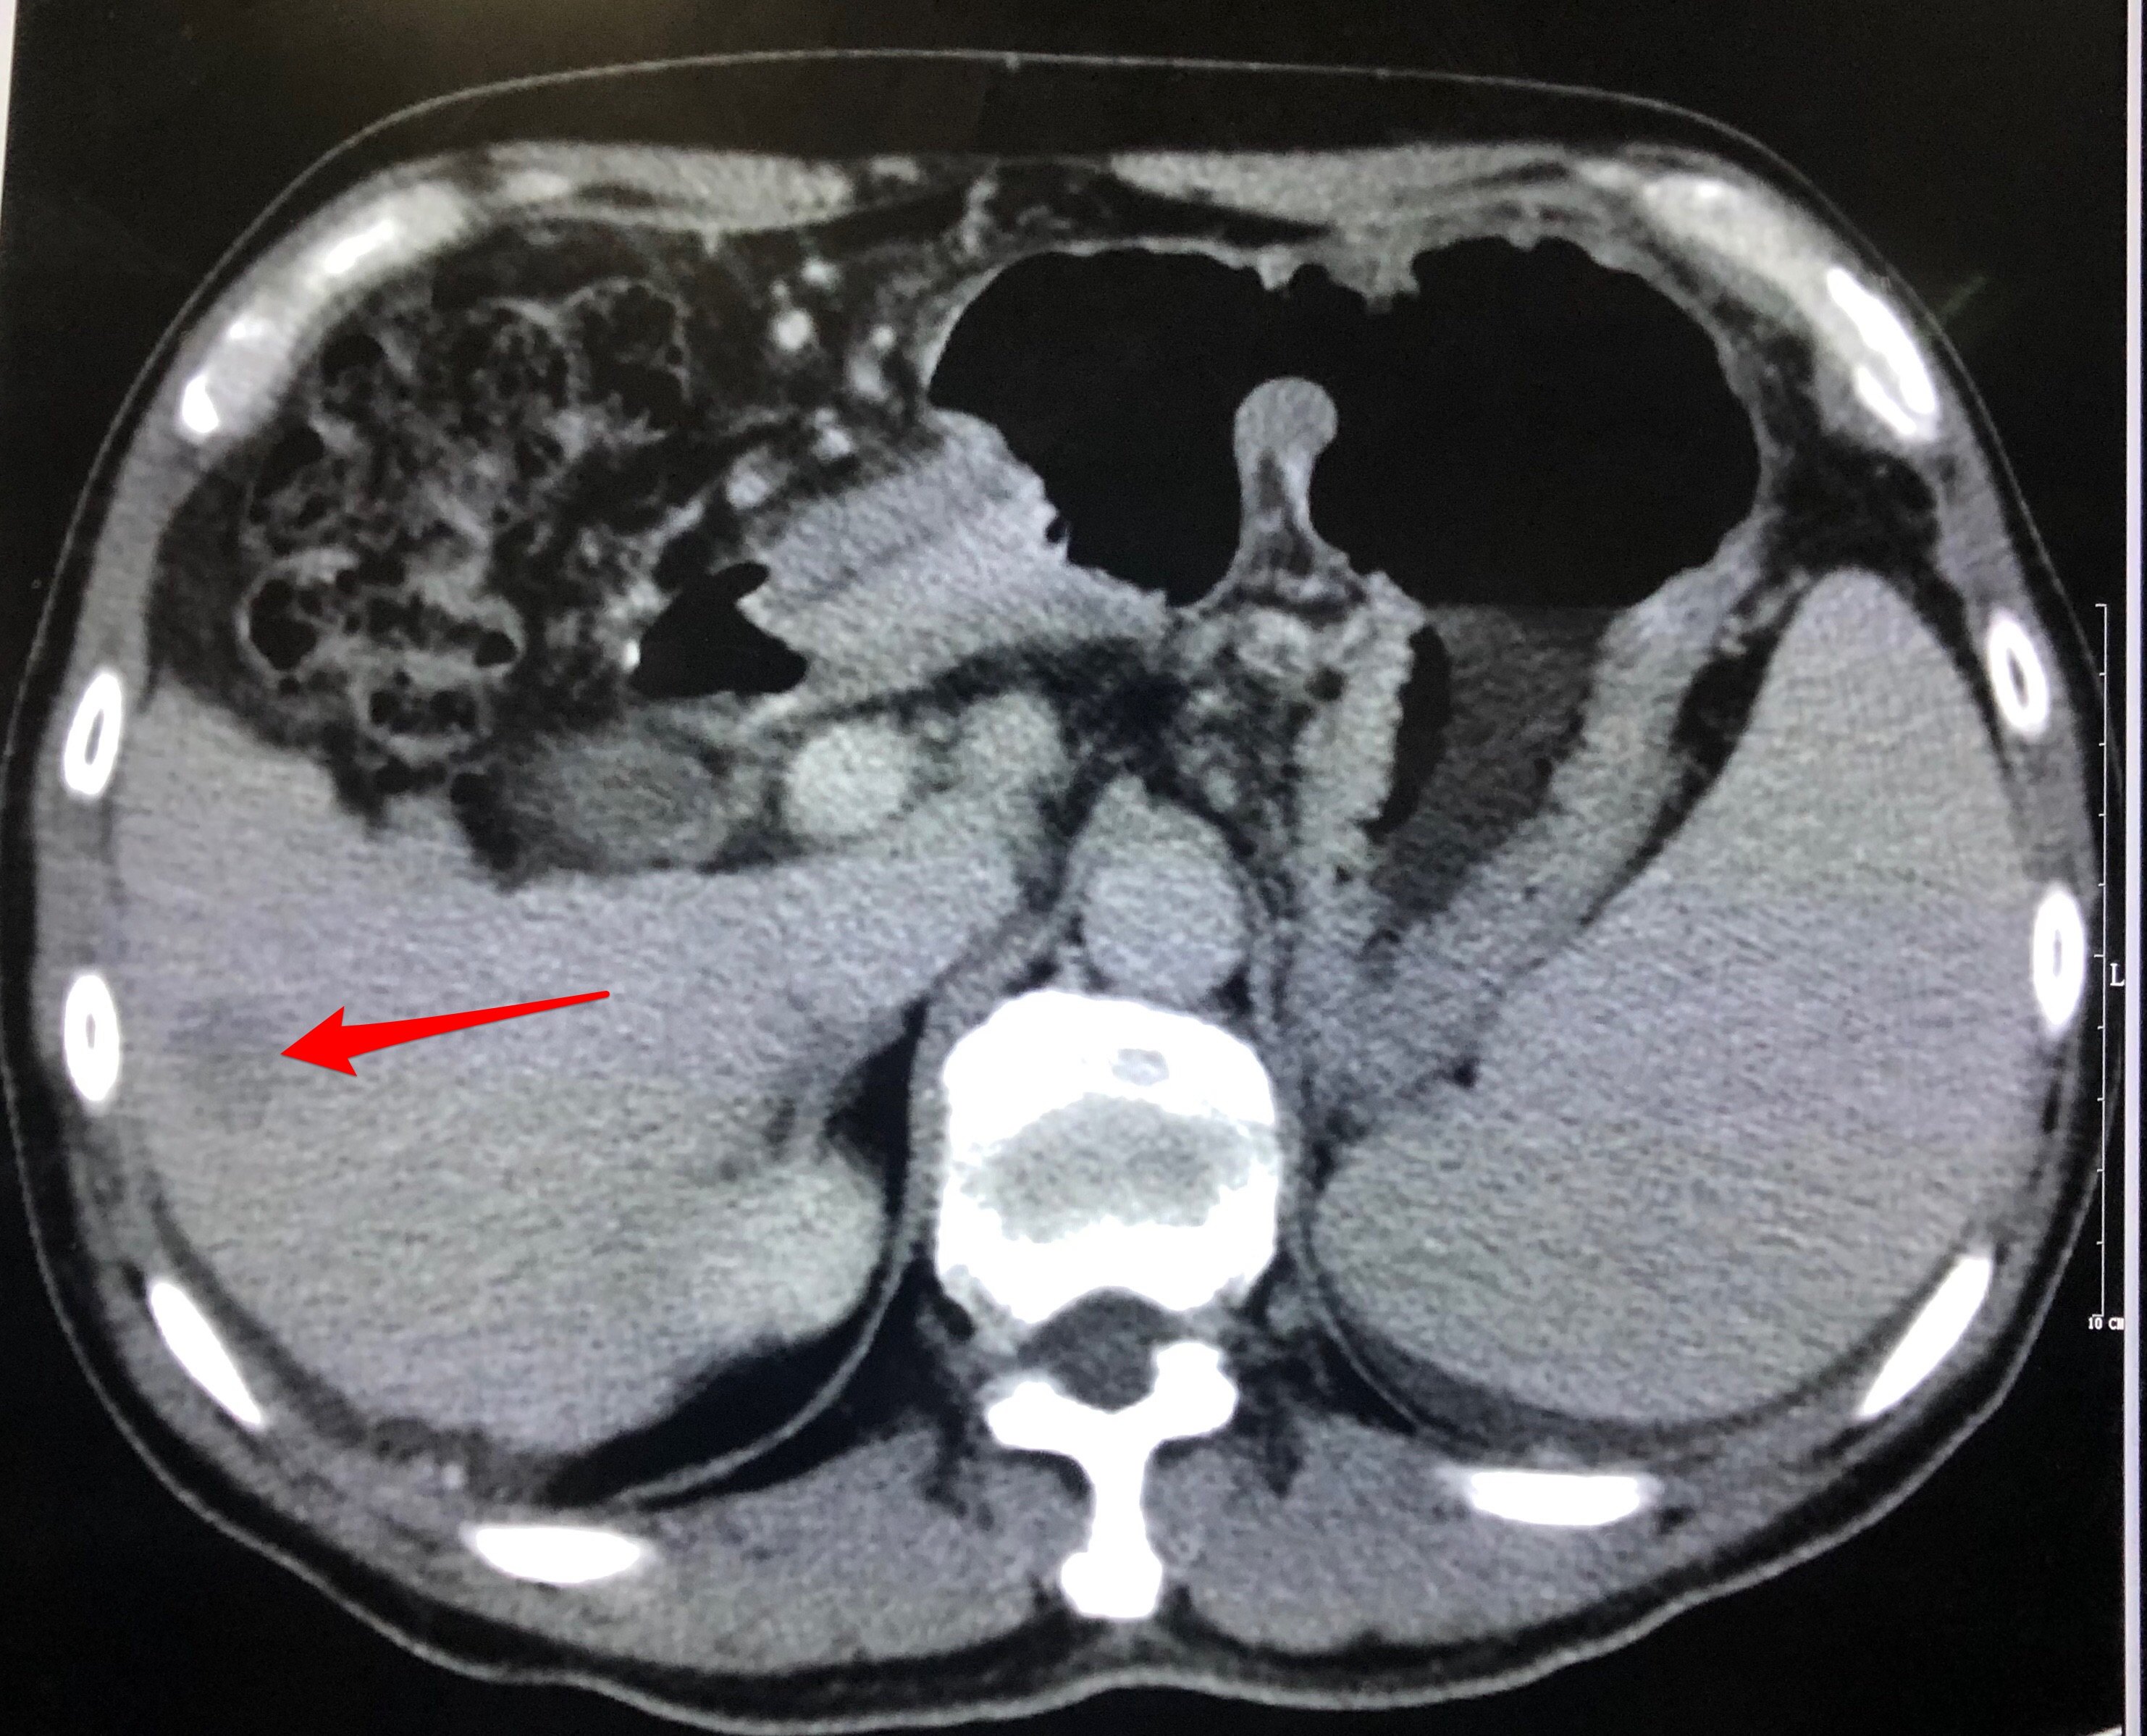

腹腔动脉造影见脾动脉粗大,肝动脉细小,提示脾动脉盗血综合症。